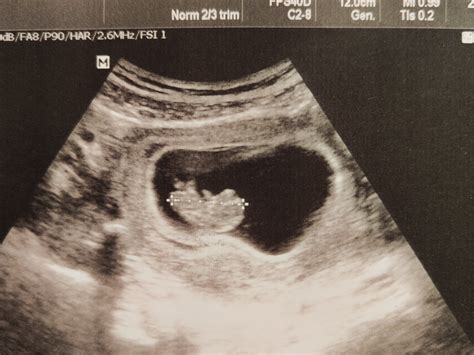

- Gynekológia a pôrodníctvo: Monitorovanie tehotenstva, hodnotenie maternice a vaječníkov.

V štyridsiatych rokoch minulého storočia začali Ludwig a Stuters používať pulzný ultrazvuk na detekciu žlčníkových kameňov. V roku 1956 Ian Donald v praxi skutočne použil jednorozmerný režim (ultrazvuk v režime A) na meranie priemeru parietálneho laloku hlavy plodu. O dva roky neskôr Donald a Brown zverejnili ultrazvukové snímky nádorov ženských pohlavných orgánov. Súčasne Brown vynašiel „dvojrozmerný skener zlúčenín“, ktorý umožňuje skúšajúcim pozorovať a analyzovať hustotu tkanív. Toto sa často označuje ako bod zlomu v lekárskej aplikácii ultrazvuku.